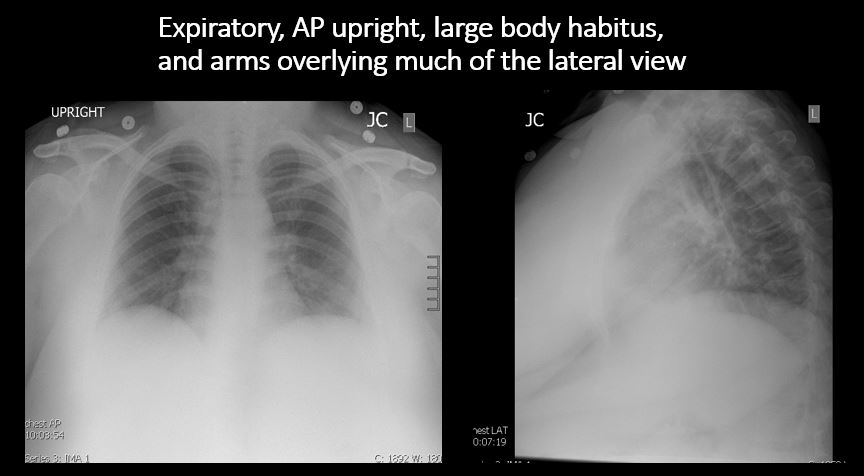

Section 1 Submit Findings Case322 Findings Technique The exam is expiratory, rotated, over or under penetrated, or limited by overlying structures or soft tissues, body habitus, patient positioning, or motion. Yes No Support Devices There is a vascular line or lines present in an abnormal location or otherwise abnormal. Yes No There are other devices such as a chest tube or pleural drain, feeding, NG, or gastrostomy tube, LVAD or pacemaker, vascular stents, cardiac valves, anesthesia catheter, VP shunt, neurostimulator, or other drains or tubes present that are in an abnormal position or are otherwise abnormal. Yes No Cardiomediastinum The superior mediastinum is abnormally widened considering the technique. Yes No There is abnormal shift of the mediastinum. Yes No There is a mass or other abnormal density in or overlying the mediastinum. Yes No There is an abnormality in the retrosternal, retrotracheal, or retrocardiac space on the lateral view. Yes No There is abnormal tracheal deviation or narrowing on the frontal and/or lateral view. Yes No There is pneumomediastinum and/or pneumopericardium. Yes No There is enlargement of the cardiac silhouette. Yes No The heart borders are abnormal. Yes No The right paratracheal stripe is thickened or enlarged. Yes No The azygoesophageal recess is displaced or otherwise obscured. Yes No Vasculature and Hila The aorta is dilated, tortuous, ectatic, calcified, or there is a focal contour abnormality. Yes No The central pulmonary arteries or hila are enlarged. Yes No The aorto-pulmonary window is convex or obscured by a mass, adenopathy, or vasculature. Yes No There is cephalization or haziness of the pulmonary vessels or congestion of the central pulmonary vasculature. Yes No Lungs The lungs are hyperinflated or underinflated generally or segmentally. Yes No There is focal, multifocal, or diffuse airspace disease, mass, opacity, or nodularity. Yes No There is focal or diffuse interstitial disease. Yes No There is focal or lobar atelectasis or total collapse of the lung. Yes No There is cavitary or cystic disease with or without air fluid levels or soft tissue nodularity. Yes No The position of the major and minor fissures is abnormal. Yes No The right or left hemidiaphragm is focally or diffusely obscured on the frontal and/or lateral view. Yes No There is elevation, depression, or contour abnormality of the right or left hemidiaphragm. Yes No Pleura There is focal or diffuse abnormality of the pleura or chest wall. Yes No There is a pleural effusion, blunting of the costophrenic angle, or posterior sulci. Yes No There is focal fluid in the fissures. Yes No There is asymmetric pleural thickening or capping of the apices. Yes No There is a pneumothorax, hydro/pneumothorax, or hemo/pneumothorax. Yes No Bones, Soft Tissues, Upper Abdomen The ribs, clavicles, shoulder, spine, or other visualized bones are abnormal. Yes No There is free air beneath the diaphragm. Yes No The bowel or organs of the upper abdomen are abnormal. Yes No There is subcutaneous emphysema, focal or diffuse soft tissue abnormality, radiopaque foreign body, or post-surgical change or hardware. Yes No